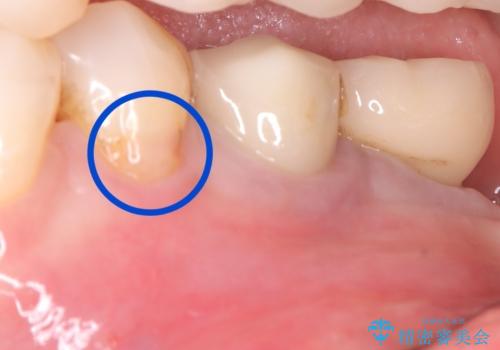

左下4番の歯頚部に知覚過敏症状を認めました。

5級窩洞のコンポジットレジン修復を過去に行ったおり、そのレジンも一部欠けてしまっている状態でした。

咬合力、食いしばりが強く他の歯にも知覚過敏症状が出ているような口腔内で、審美性良く劣化しない丈夫な修復を希望されたため、セラミッククラウンでの治療となりました。